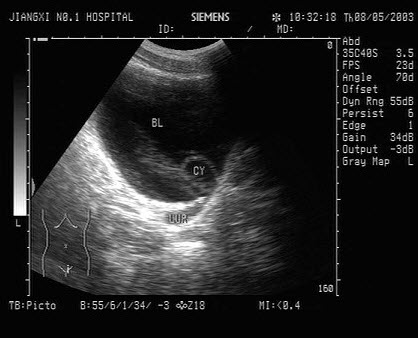

23、单项选择题

患者男46岁,既往有胆囊结石病史,上腹部疼痛不适年余,加重1个月,皮肤、巩膜轻度黄染,B超检查如图所示,根据超声声像图,诊断为()

A.胆囊结石并胆囊炎,肝血管瘤

B.胆囊结石并胆汁淤积,肝血管瘤

C.胆囊结石并胆囊癌,肝转移性癌

D.胆囊结石并肝癌

E.胆囊结石并胆息肉,肝转移性癌